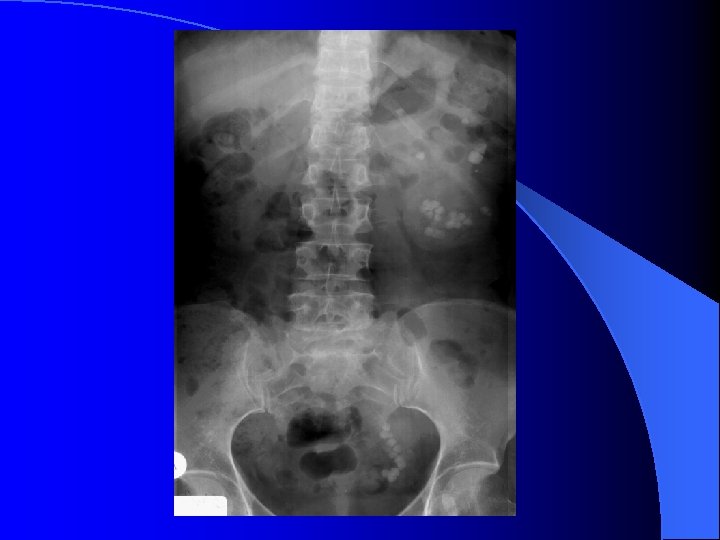

UIV l Timp parenchimatos – nefrograma – sub 1 min. de la terminarea injectării – nefrotomografie l Timp excretor – urograma – ~ 3 min. de la terminarea injectării – opacifierea căilor excretorii – uzual clişee la 5, 15 şi 30 min.

UIV - variante NU EXISTĂ UIV STANDARD!!! l Compresie ureterală – zona iliacă l – opacifiere optimă a SPC şi ureterelor – contraindicaţii – colica renală – traumatismele aparatului urinar – anevrism aorta abdominală Decubit ventral –rezultate similare compresiei l Încărcare cu apă – ingestie 500 ml lichid/furosemid 40 mg i. v. – disfuncţia de joncţiune l Clişeu postmicţional – rezidiu l UIV minutată l

UIV l Indicaţii – sindrom obstructiv – sindr. de masă tumorală renală/urotelială – traumatisme aparat urinar l Limite – insuficienţa renală – colica renală – tumori de dimensiuni mici – pneumatizare intestinală